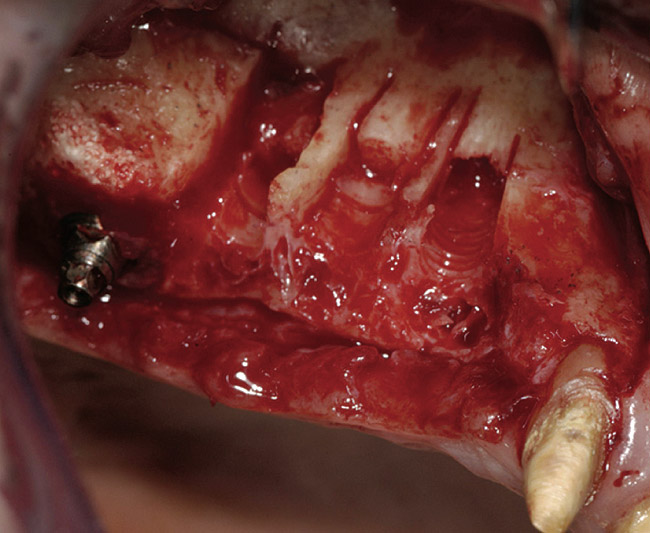

A 72-year-old man was referred for removal of failing maxillary right posterior implants (Figure 19). The treatment plan included removal of three implants with simultaneous bone augmentation and replacement implants for implant-supported fixed bridgework. Implant removal and bone grafting with rhPDGF (Gem 21®, Osteohealth, www.osteohealth.com) and allograft (MinerOss) and xenograft (BioOss®, Geistlick, www.geistlickonline.com) were used along with titanium mesh for space maintenance (Figure 20, Figure 21 and Figure 22). Six months later, mesh removal revealed type I bone allowing for placement of three implants (Figure 23 and Figure 24).

Figure 21  Bone grafting with rhPDGF, allograft, and xenograft.

Figure 21

Figure 22  Titanium mesh fixation.

Figure 22

Figure 23  Trephinated core biopsy obtained at 5 months.

Figure 23

Figure 24  Histology: Note active osteocytes with new bone formation.

Figure 24